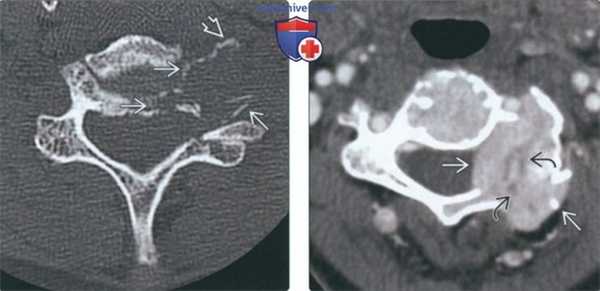

3. КТ при литических и бластических метастазах в шейные позвонки:

• КТ без КУ:

о Деструкция кортикальной и губчатой кости:

- Литические очаги без склеротического ободка, с географическими краями; матрикс опухоли отсутствует

о Паравертебральная и/или эпидуральная мягкотканная опухоль

о ± патологический перелом:

- При «доброкачественном» компрессионном переломе может наблюдаться «ободок» (отек или гематома) в мягких тканях, обычно < 5 мм

о Склеротические метастазы редко связаны с переломом или мягкотканной опухолью

• КТ с КУ:

о Вариабельное контрастирование

(Слева) На аксиальной КТ без КУ определяется типичный метастаз с деструкцией кости. Не путайте костные фрагменты, напоминающие яичную скорлупу, с опухолевым кальцинатами.

(Справа) На аксиальной КТА определяется мягкотканная опухоль (метастаз рака щитовидной железы) с интенсивным накоплением контраста, свидетельствующим о гиперваскулярности. Мелкие неконтрастирующи-еся очаги в центре представляют собой зоны некроза. Метастазы почечноклеточного рака и меланомы преимущественно являются гиперваскулярными и экспансивными.